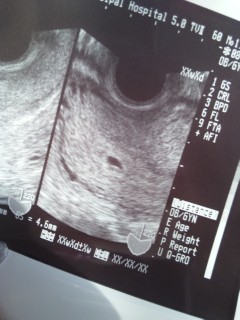

4週4日で受診し、何も見えず、早いですが待ちきれずまた産婦人科へ。5週にしてようやく会えました。ぼやっと写った赤ちゃんの袋をみたときの感動は忘れられません!成長が楽しみです!

ちっちゃーい。

けどむっちゃ可愛い(*^_^*)

これから頑張ります☆